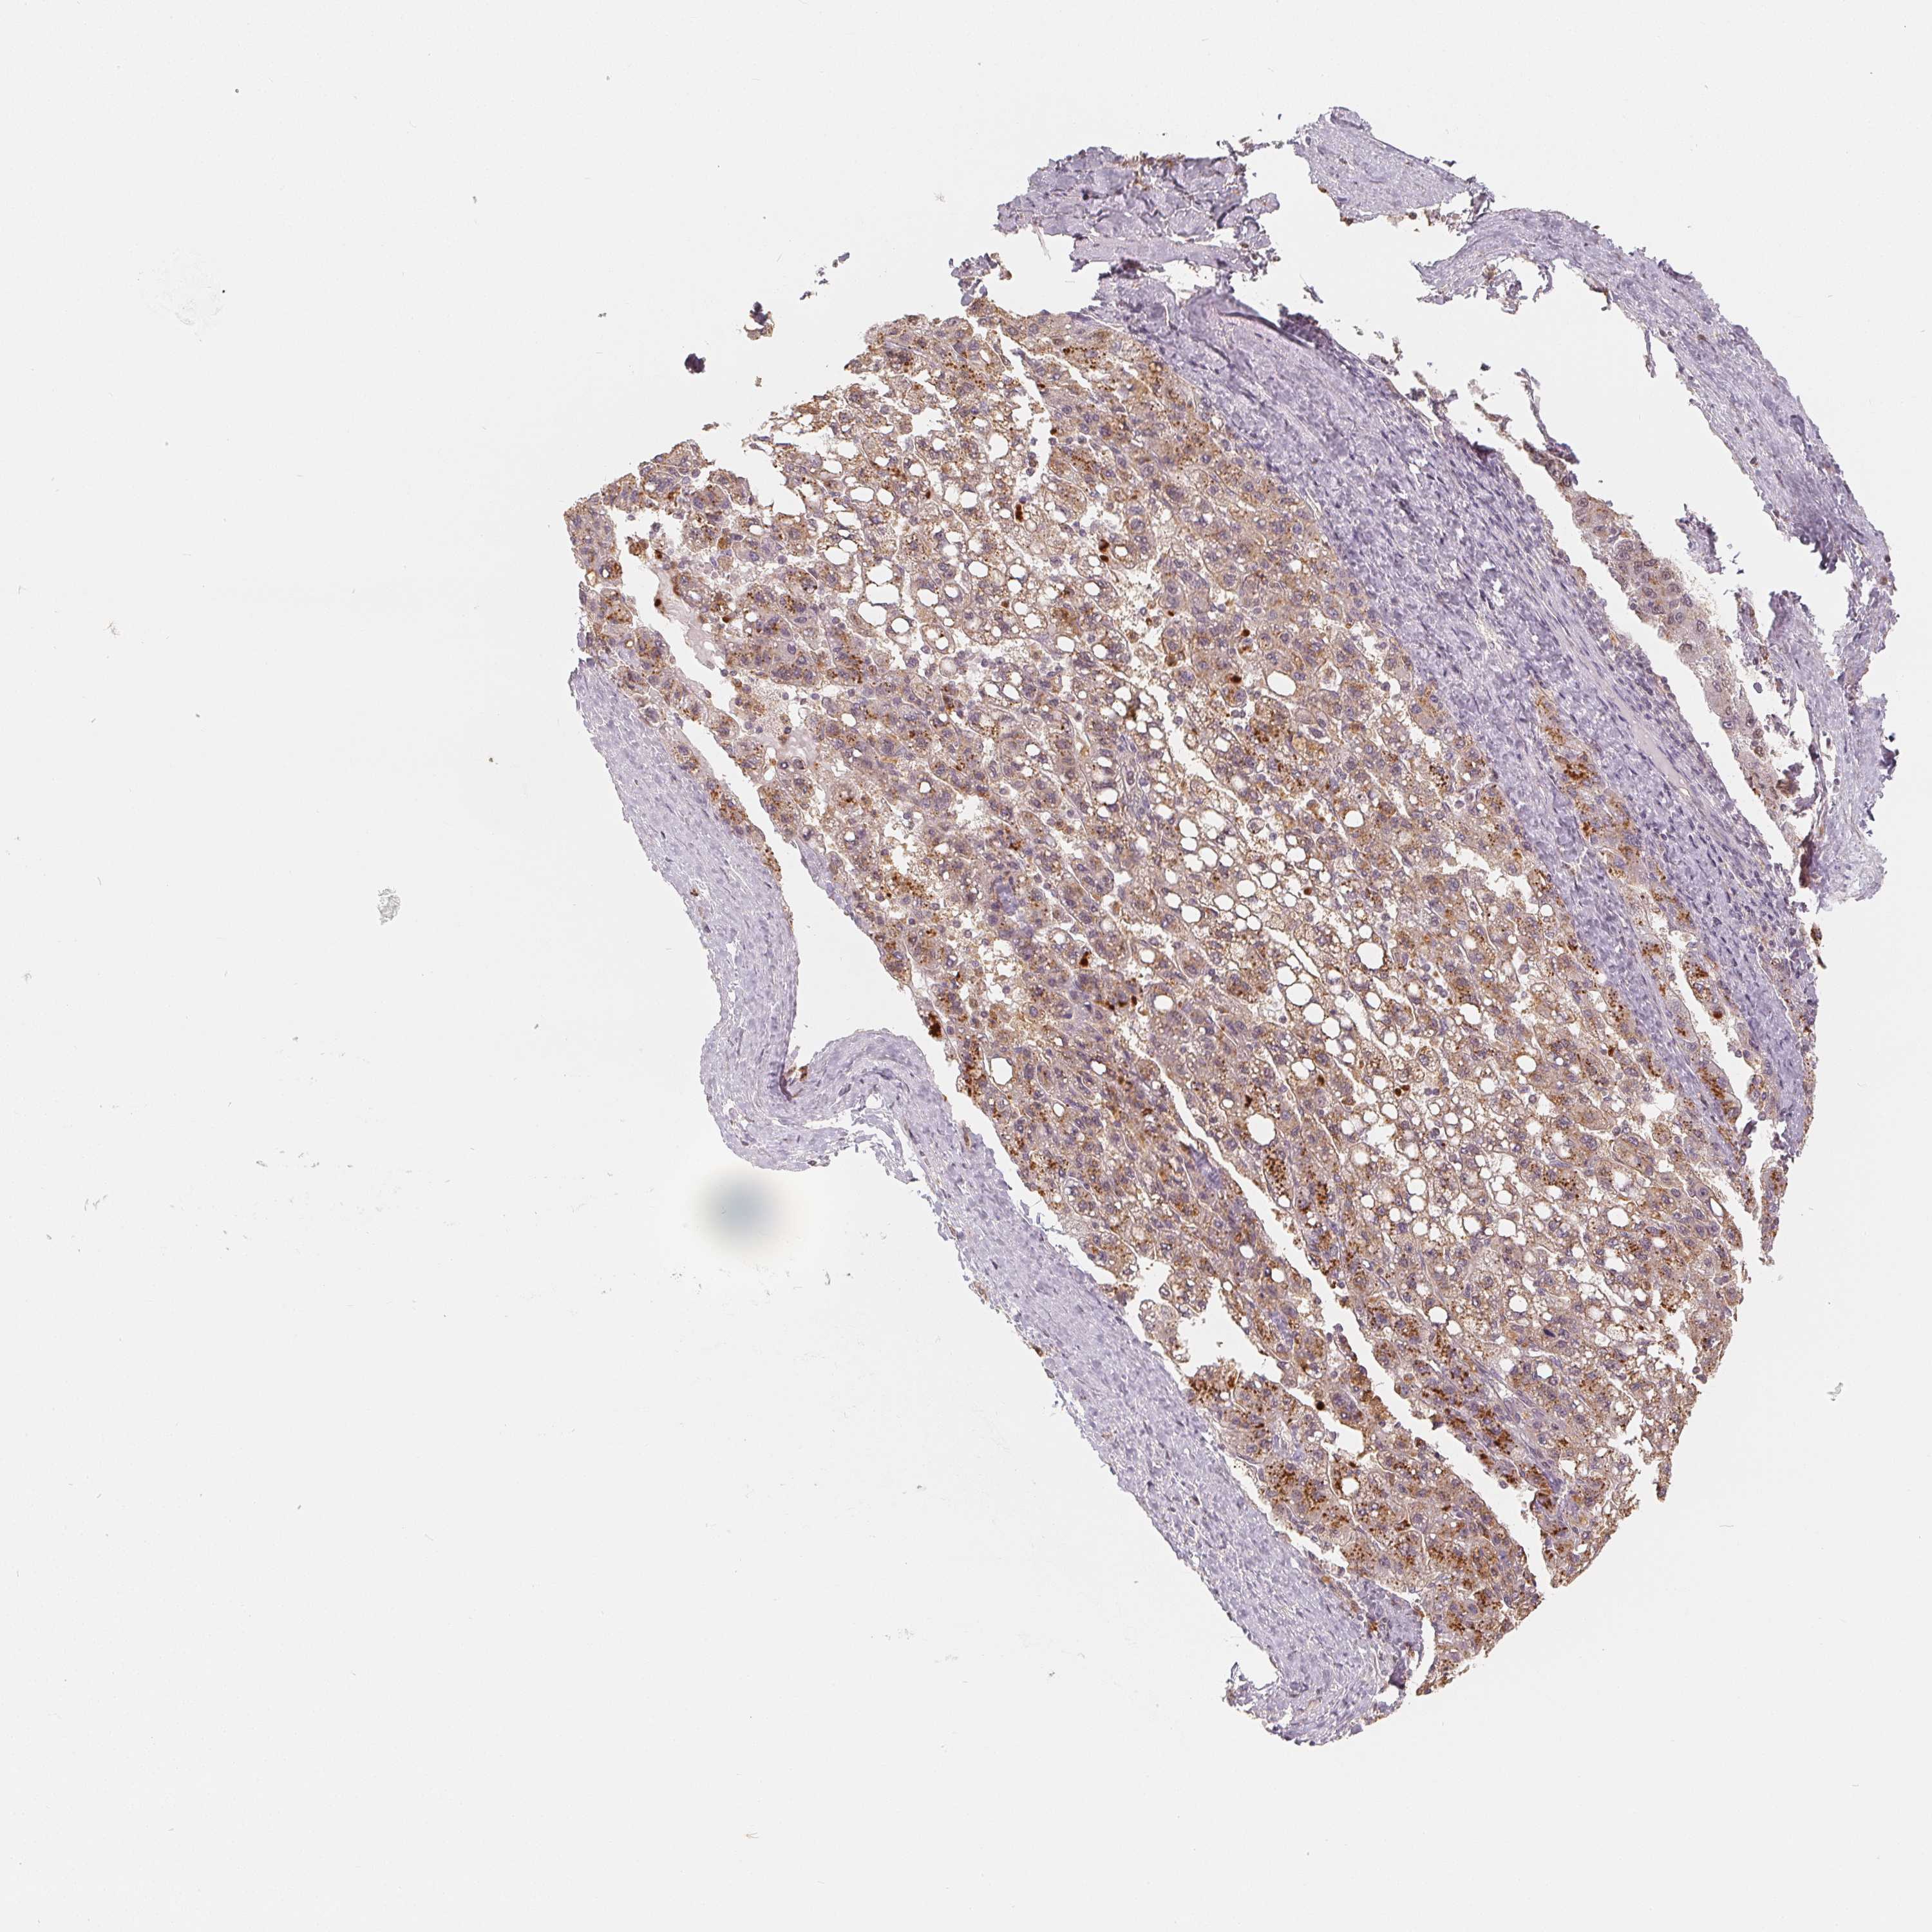

LIVER CANCER - Protein expressioni

A mouse-over function shows sample information and annotation data. Click on an image to view it in a full screen mode. Samples can be filtered based on level of antibody staining by selecting one or several of the following categories: high, medium, low and not detected. The assay and annotation is described here.

Antibody stainingi

Antibody staining in the annotated cell types in the current human tissue is reported as not detected, low, medium, or high, based on conventional immunohistochemistry profiling in selected tissues. This score is based on the combination of the staining intensity and fraction of stained cells.

Each image is clickable and will lead to virtual microscopy that enables deeper exploration of all samples and also displays staining intensity scores, fraction scores and subcellular localization as well as patient and tissue information for each sample.

Antibody HPA036322

Antibody HPA036323

Staining

High

Medium

Low

Not detected

Intensity

Strong

Moderate

Weak

Negative

Quantity

>75%

75%-25%

<25%

None

Location

Nuclear

Cytoplasmic/membranous

Cytoplasmic/membranous,nuclear

Cholangiocarcinoma

Carcinoma, Hepatocellular, NOS